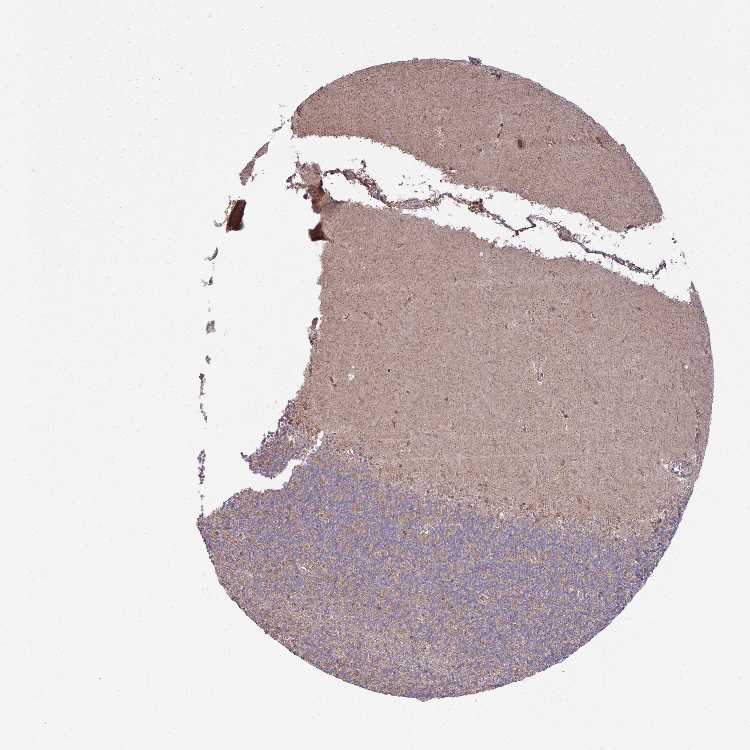

CEREBELLUM - Antibody stainingi

Antibody staining in the annotated cell types in the current human tissue is reported as not detected, low, medium, or high, based on conventional immunohistochemistry profiling in selected tissues. This score is based on the combination of the staining intensity and fraction of stained cells.

Each image is clickable and will lead to virtual microscopy that enables deeper exploration of all samples and also displays staining intensity scores, fraction scores and subcellular localization as well as patient and tissue information for each sample.

Antibody HPA040026Antibody HPA044090Antibody CAB008672

Purkinje cells Not detectedMediumNot detected

Cells in granular layer Not detectedLowNot detected

Cells in molecular layer Not detectedNot detectedLow